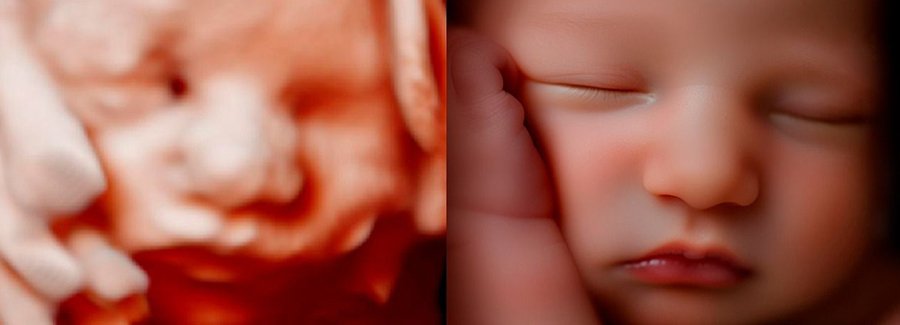

Often referred to as 5D, HD or FRV (fetal realistic view), 5D/HD is the newest development in pregnancy imaging. It captures and combines high definition volume data to create automated images with amazing color and clarity so you can see your baby as though you were looking from inside the womb.